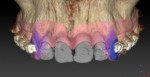

C | Invivo 5

Figure 3 | Invivo™ 5 is comprehensive 3D imaging software that broadly covers diagnosis, treatment planning, custom appliance ordering, and cloud data. Users don’t need to switch software for each task, providing you with a convenient, easy imaging application right at your fingertips.

408-885-1474

dental.anatomage.com